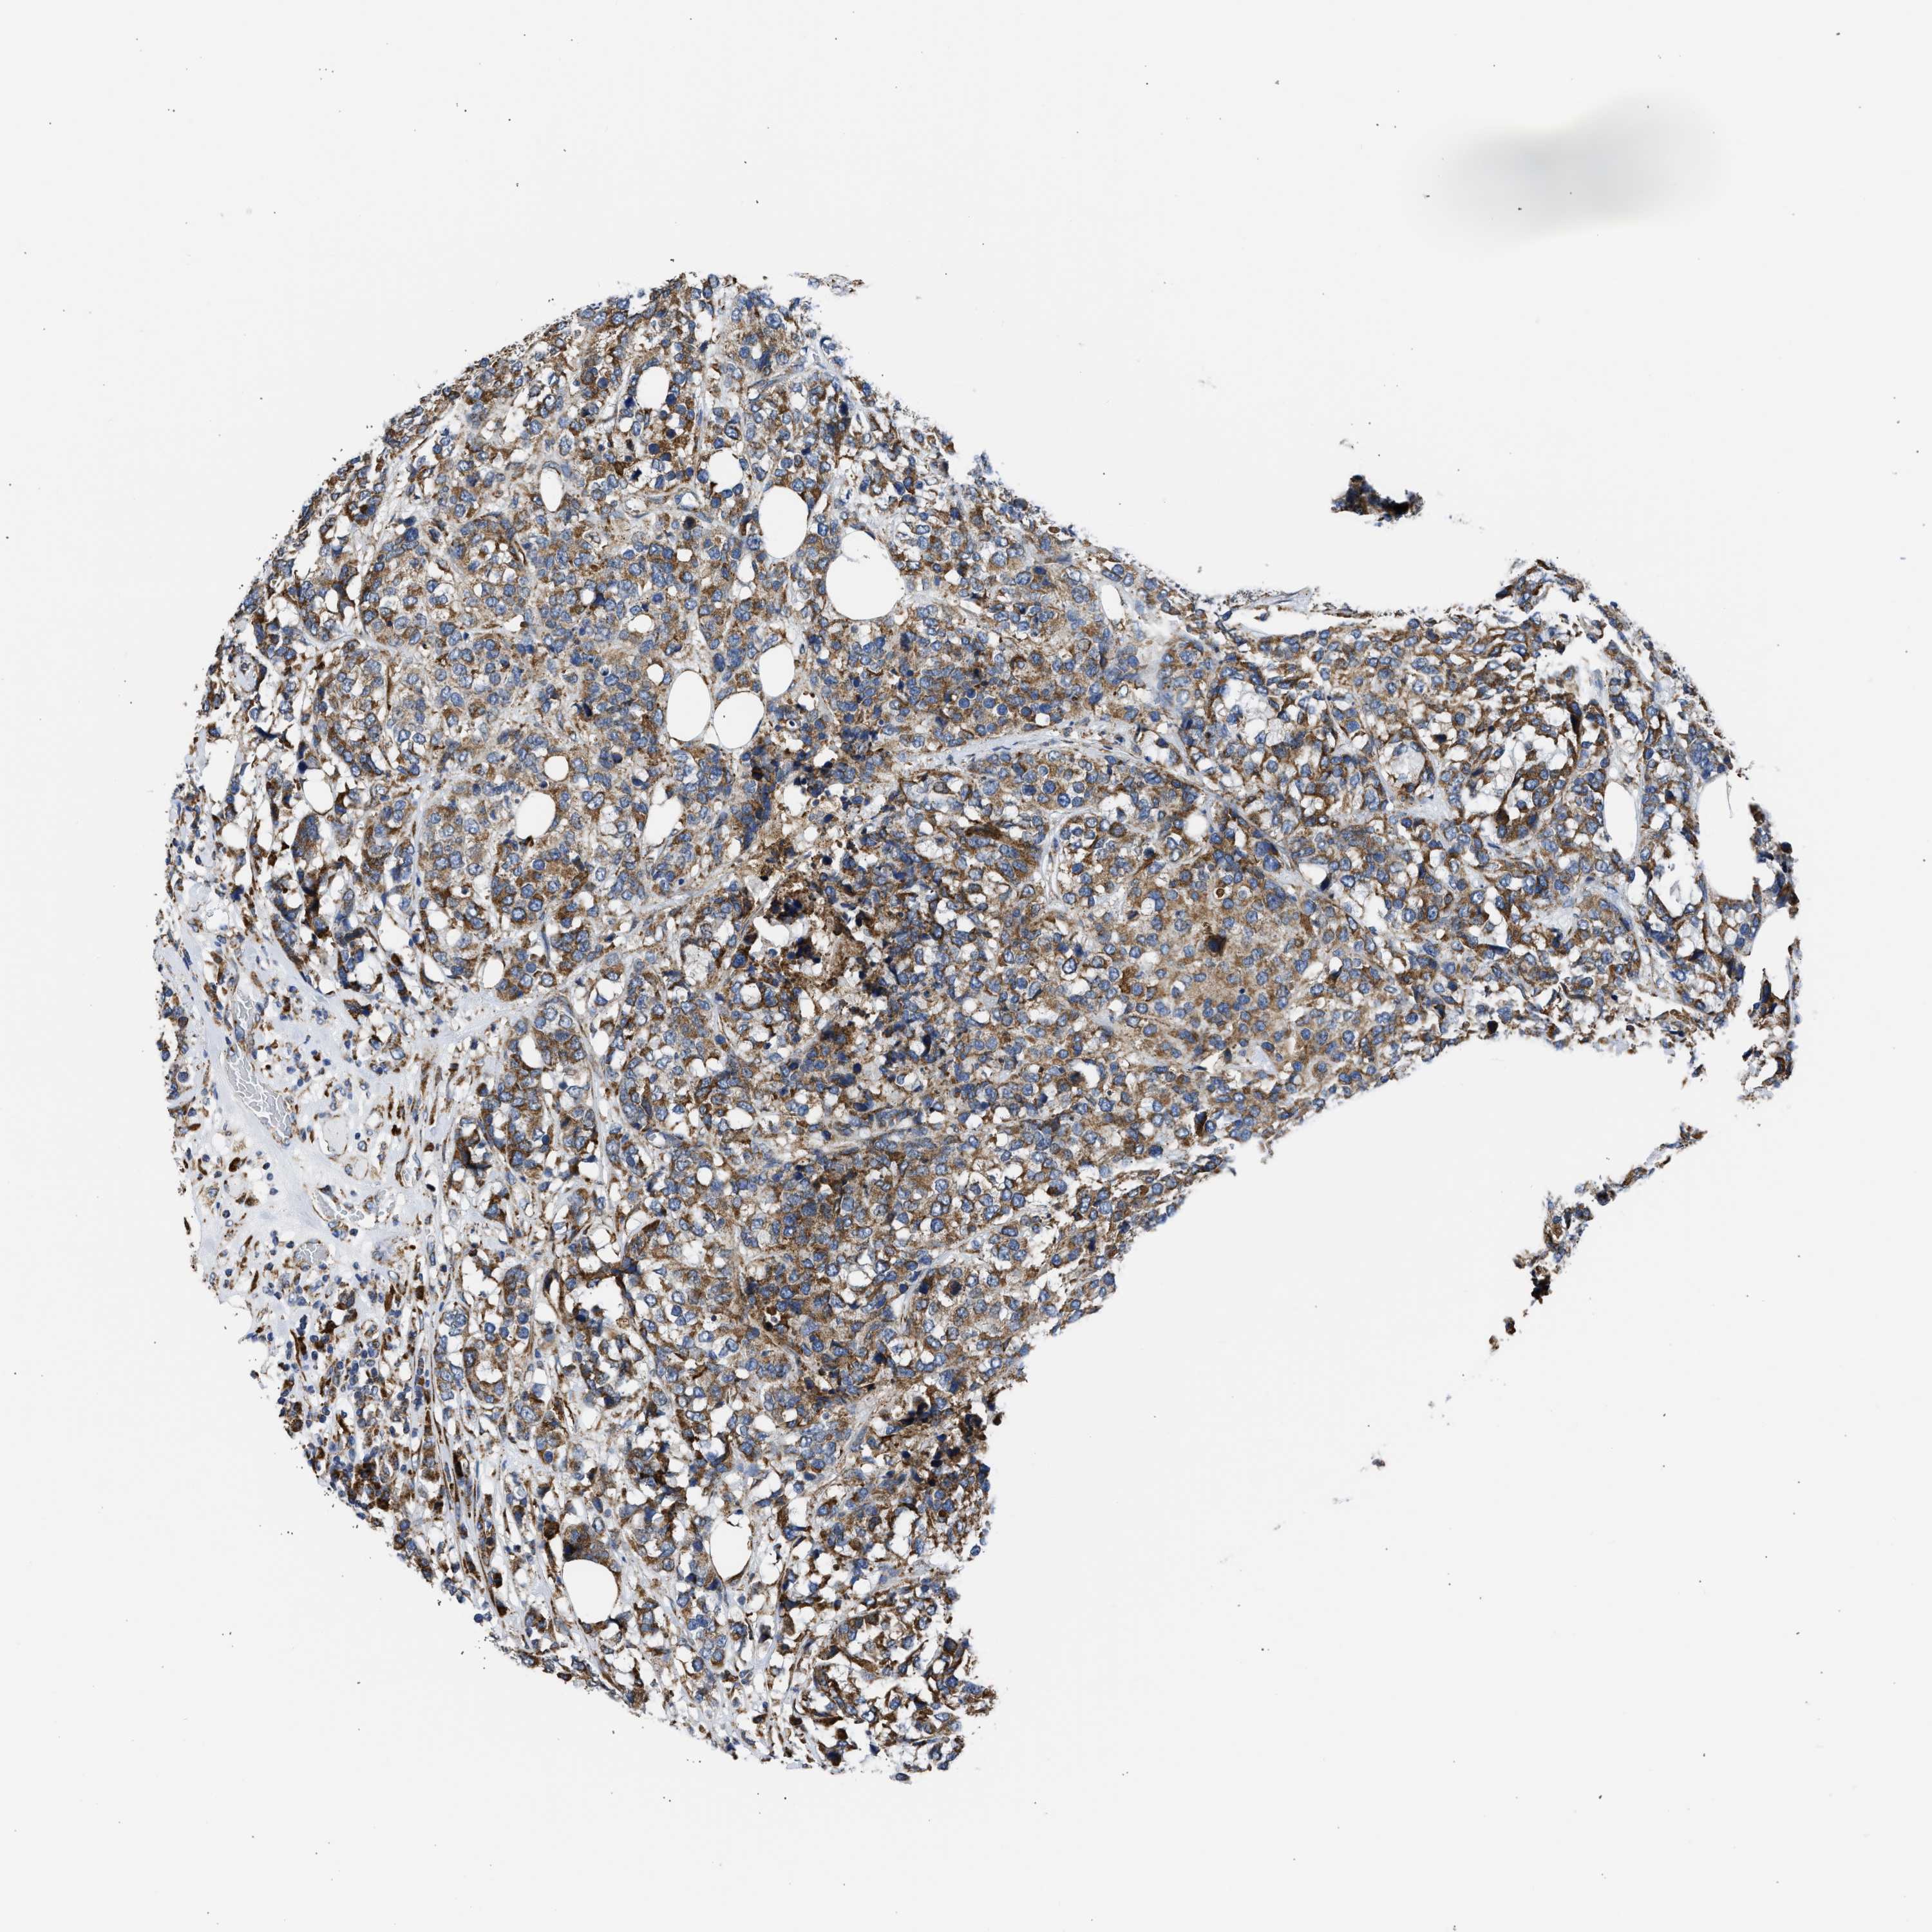

CANCER BREAST CANCER Show tissue menu

BRCA TCGA BRCA VALIDATION PROTEIN EXPRESSION